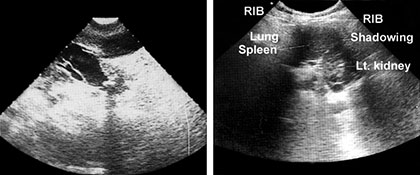

Water is a very good conductor of ultrasound. Water within the body such as cyst and urine filled bladder, form ultrasonic window through which underlying tissues can be easily imaged. Lungs has much higher attenuation rate than either air or soft tissue.

This is because the small pocket of air in alveoli are very efficient in scattering ultrasound energy. Because of this, normal lung structure is extremely difficult to penetrate with sound waves.

Bone shields some part of the body against easy access by ultrasound. Similarly bowel containing air conduct sound so poorly that they can not be imaged with ultrasound.

A neighbouring soft tissue or fluid filled organ must be used as a window to image a structure that is obscured by air (Fig. 1.9).

Structure of differing acoustic impedance (such as gall-bladder and liver) are much easier to distinguish from one another than structure of similar acoustic texture (e.g. liver and kidney) (Fig. 1.10).

If acoustic densities are vastly different, sound beam is completely reflected and total acoustic shadowing occurs.

Acoustic shadowing is observed behind bone (ribs), stones in kidney or the gallbladder and air (intestinal gas).

Echoes are not detected if no difference in acoustic densities are encountered. Homogenous fluid (urine and cyst content, but also ascites and pleural effusion) are seen as echo free (black) structure, e.g. gallbladder and hepatic vessels (Fig. 1.11).